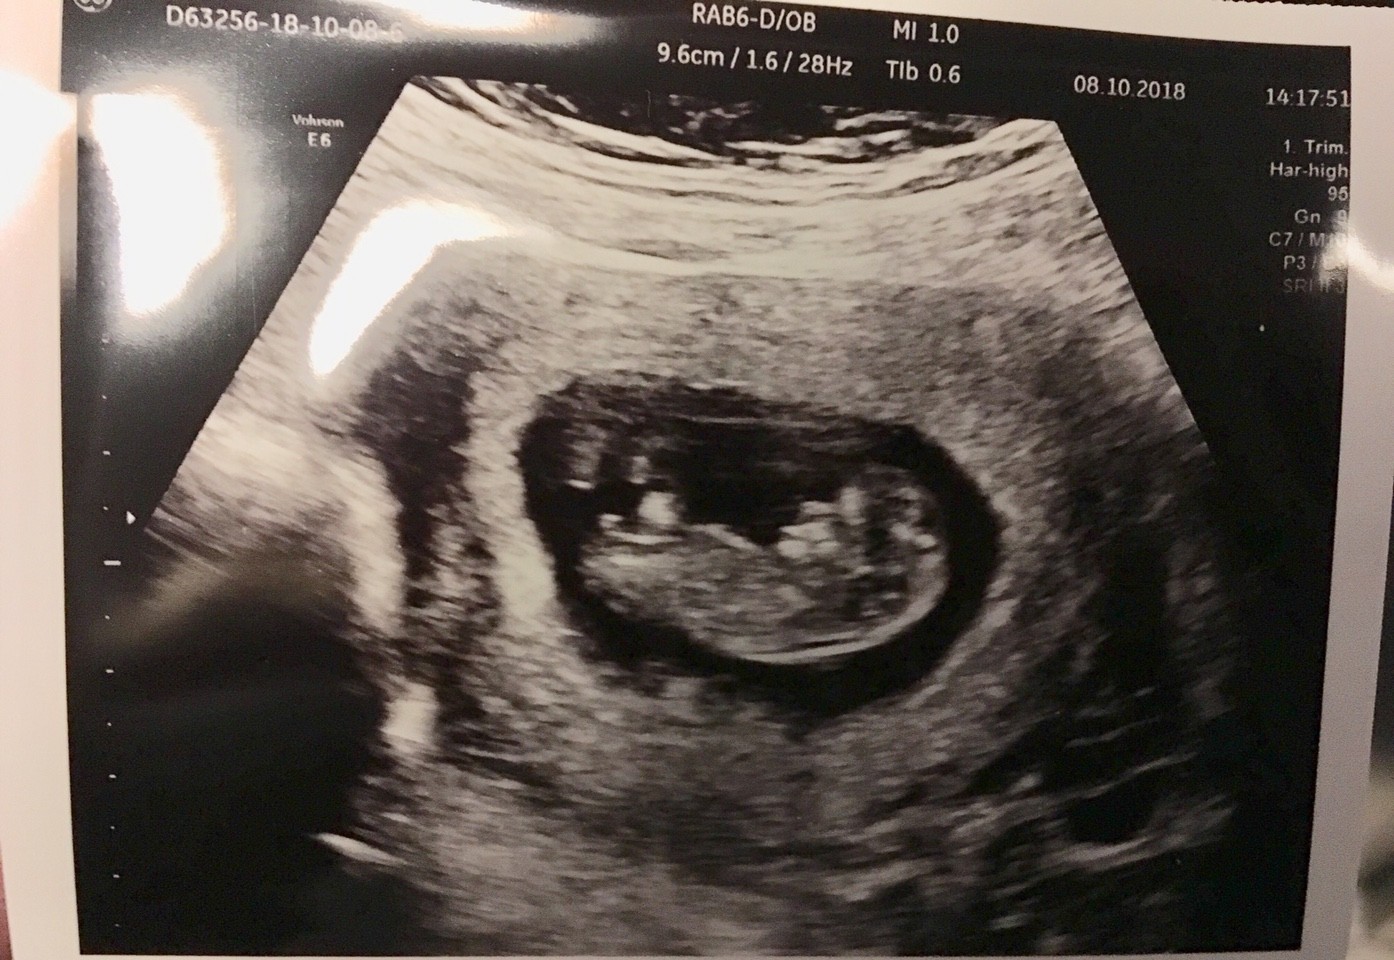

Moje zdjęcie z USG, ja tak dla odmiany, 3 razy doktora pytałam czy na pewno nie ma tam nigdzie drugiego bąbla schowanego, bo powiedział że owulacja była podwójna.... a bliźniaki w domu już mam i teraz wystarczy mi jedno na prawdę ;)

Załączniki

• IMG_2038.JPG

IMG_2038.JPG

1,4 MB · Wyświetleń: 210